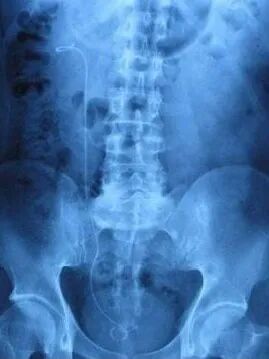

双J管,因其两头有J型的圈而得名,同时,其形状与猪尾巴非常相似,故也叫猪尾巴导管。双J管因厂家不同,材料不同外观上稍有差异,但大体上都是管子中空,其管上有多个侧孔,作用引流尿液、支撑输尿管。

先来看看它的庐山真面目: